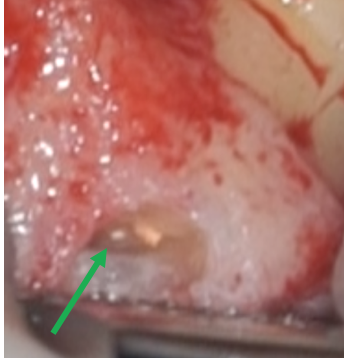

• 再根管治療時に殺菌、根管充填したMB2を確認(緑矢印)。

• 青色の細菌の染め出し液で感染源のイスムスが発覚(青矢印)。根管治療で殺菌が届かない場所です。